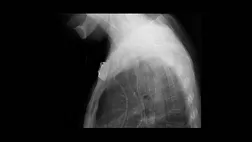

Сразу после развертывания положение стента подтверждается рентгенологическим исследованием грудной клетки. Последующее рентгеноскопическое или эндоскопическое обследование может потребоваться для оценки статуса кровотечения и планирования дальнейшего лечения. На рис. 3 показаны эндоскопические изображения, сделанные во время наблюдения, показывающие исчезновение кровотечения из варикозно расширенных вен. Обычно мы придерживаемся перорального приема в течение 24 часов. Как и при любой стандартной процедуре установки стента, рекомендуется соблюдать диету с низким содержанием остатков во избежание обструкции стента. В течение срока службы стента необходимо проводить периодические проверки на предмет возможных повреждений пищевода и миграции стента. Мигрировавший стент можно переместить или заменить.

Рис. 3 Эндоскопический вид при контрольном обследовании.